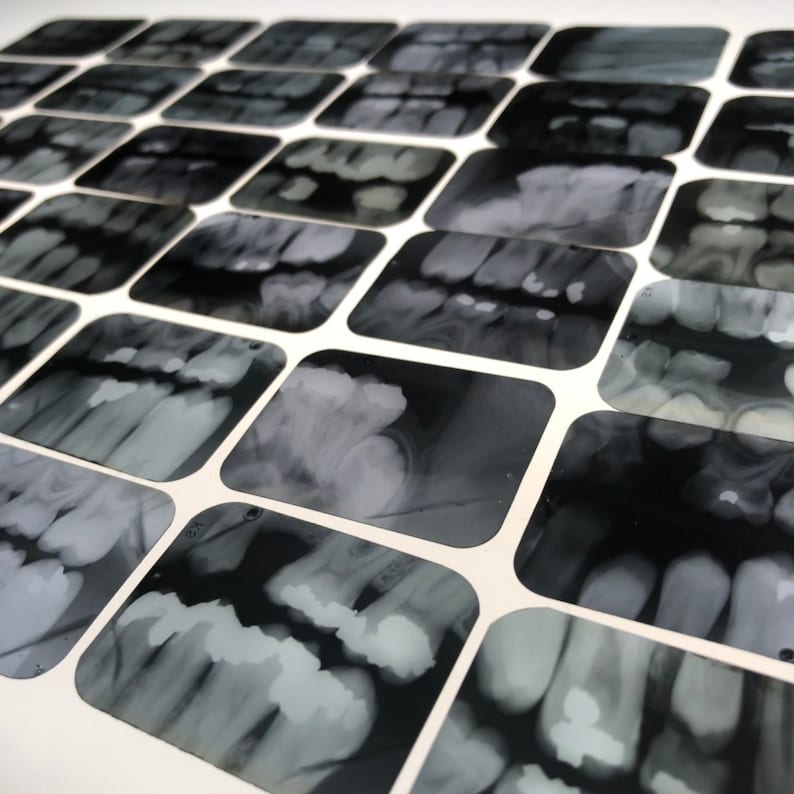

From www.etsy.com

Vintage Dental Xrays Lot of 5 old Dentist Tooth Films Etsy Conventional Dental Films the aims of the present study were (1) to evaluate the diagnostic accuracy of enamel caries lesion detection using. it addresses topics such as patient selection criteria, film selection for conventional radiographs, collimation, beam filtration, patient protective equipment, film holders, operator protection, film exposure and processing, infection control, quality assurance, image viewing, direct digital radiography and continuing education. Conventional Dental Films.

Vintage Dental Xrays Lot of 5 old Dentist Tooth Films Etsy Conventional Dental Films it addresses topics such as patient selection criteria, film selection for conventional radiographs, collimation, beam filtration, patient protective equipment, film holders, operator protection, film exposure and processing, infection control, quality assurance, image viewing, direct digital radiography and continuing education of dental health. therefore, the purpose of this study is to compare periapical radiographs. Types of digital imaging systems.. Conventional Dental Films.